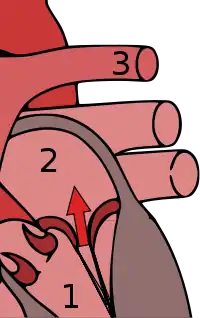

Mitral valve prolapse (MVP) is a valvular heart disease in which mitral valve leaflets enter into the left atrium when the ventricle contracts.[1] Symptoms vary from none, to chest pain, shortness of breath, palpitations, and anxiety.[1][3] Complications may include mitral regurgitation, atrial fibrillation, infective endocarditis, stroke, and cardiac arrest.[1]

Mitral valve prolapse is frequently associated with mild mitral regurgitation,[13] where blood aberrantly flows from the left ventricle into the left atrium during systole. In the United States, MVP is the most common cause of severe, non-ischemic mitral regurgitation.[14] This is occasionally due to rupture of the chordae tendineae that support the mitral valve.[11]

The mitral valve, so named because of its resemblance to a bishop's mitre, is the heart valve that prevents the backflow of blood from the left ventricle into the left atrium of the heart. It is composed of two leaflets, one anterior and one posterior, that close when the left ventricle contracts.[41]